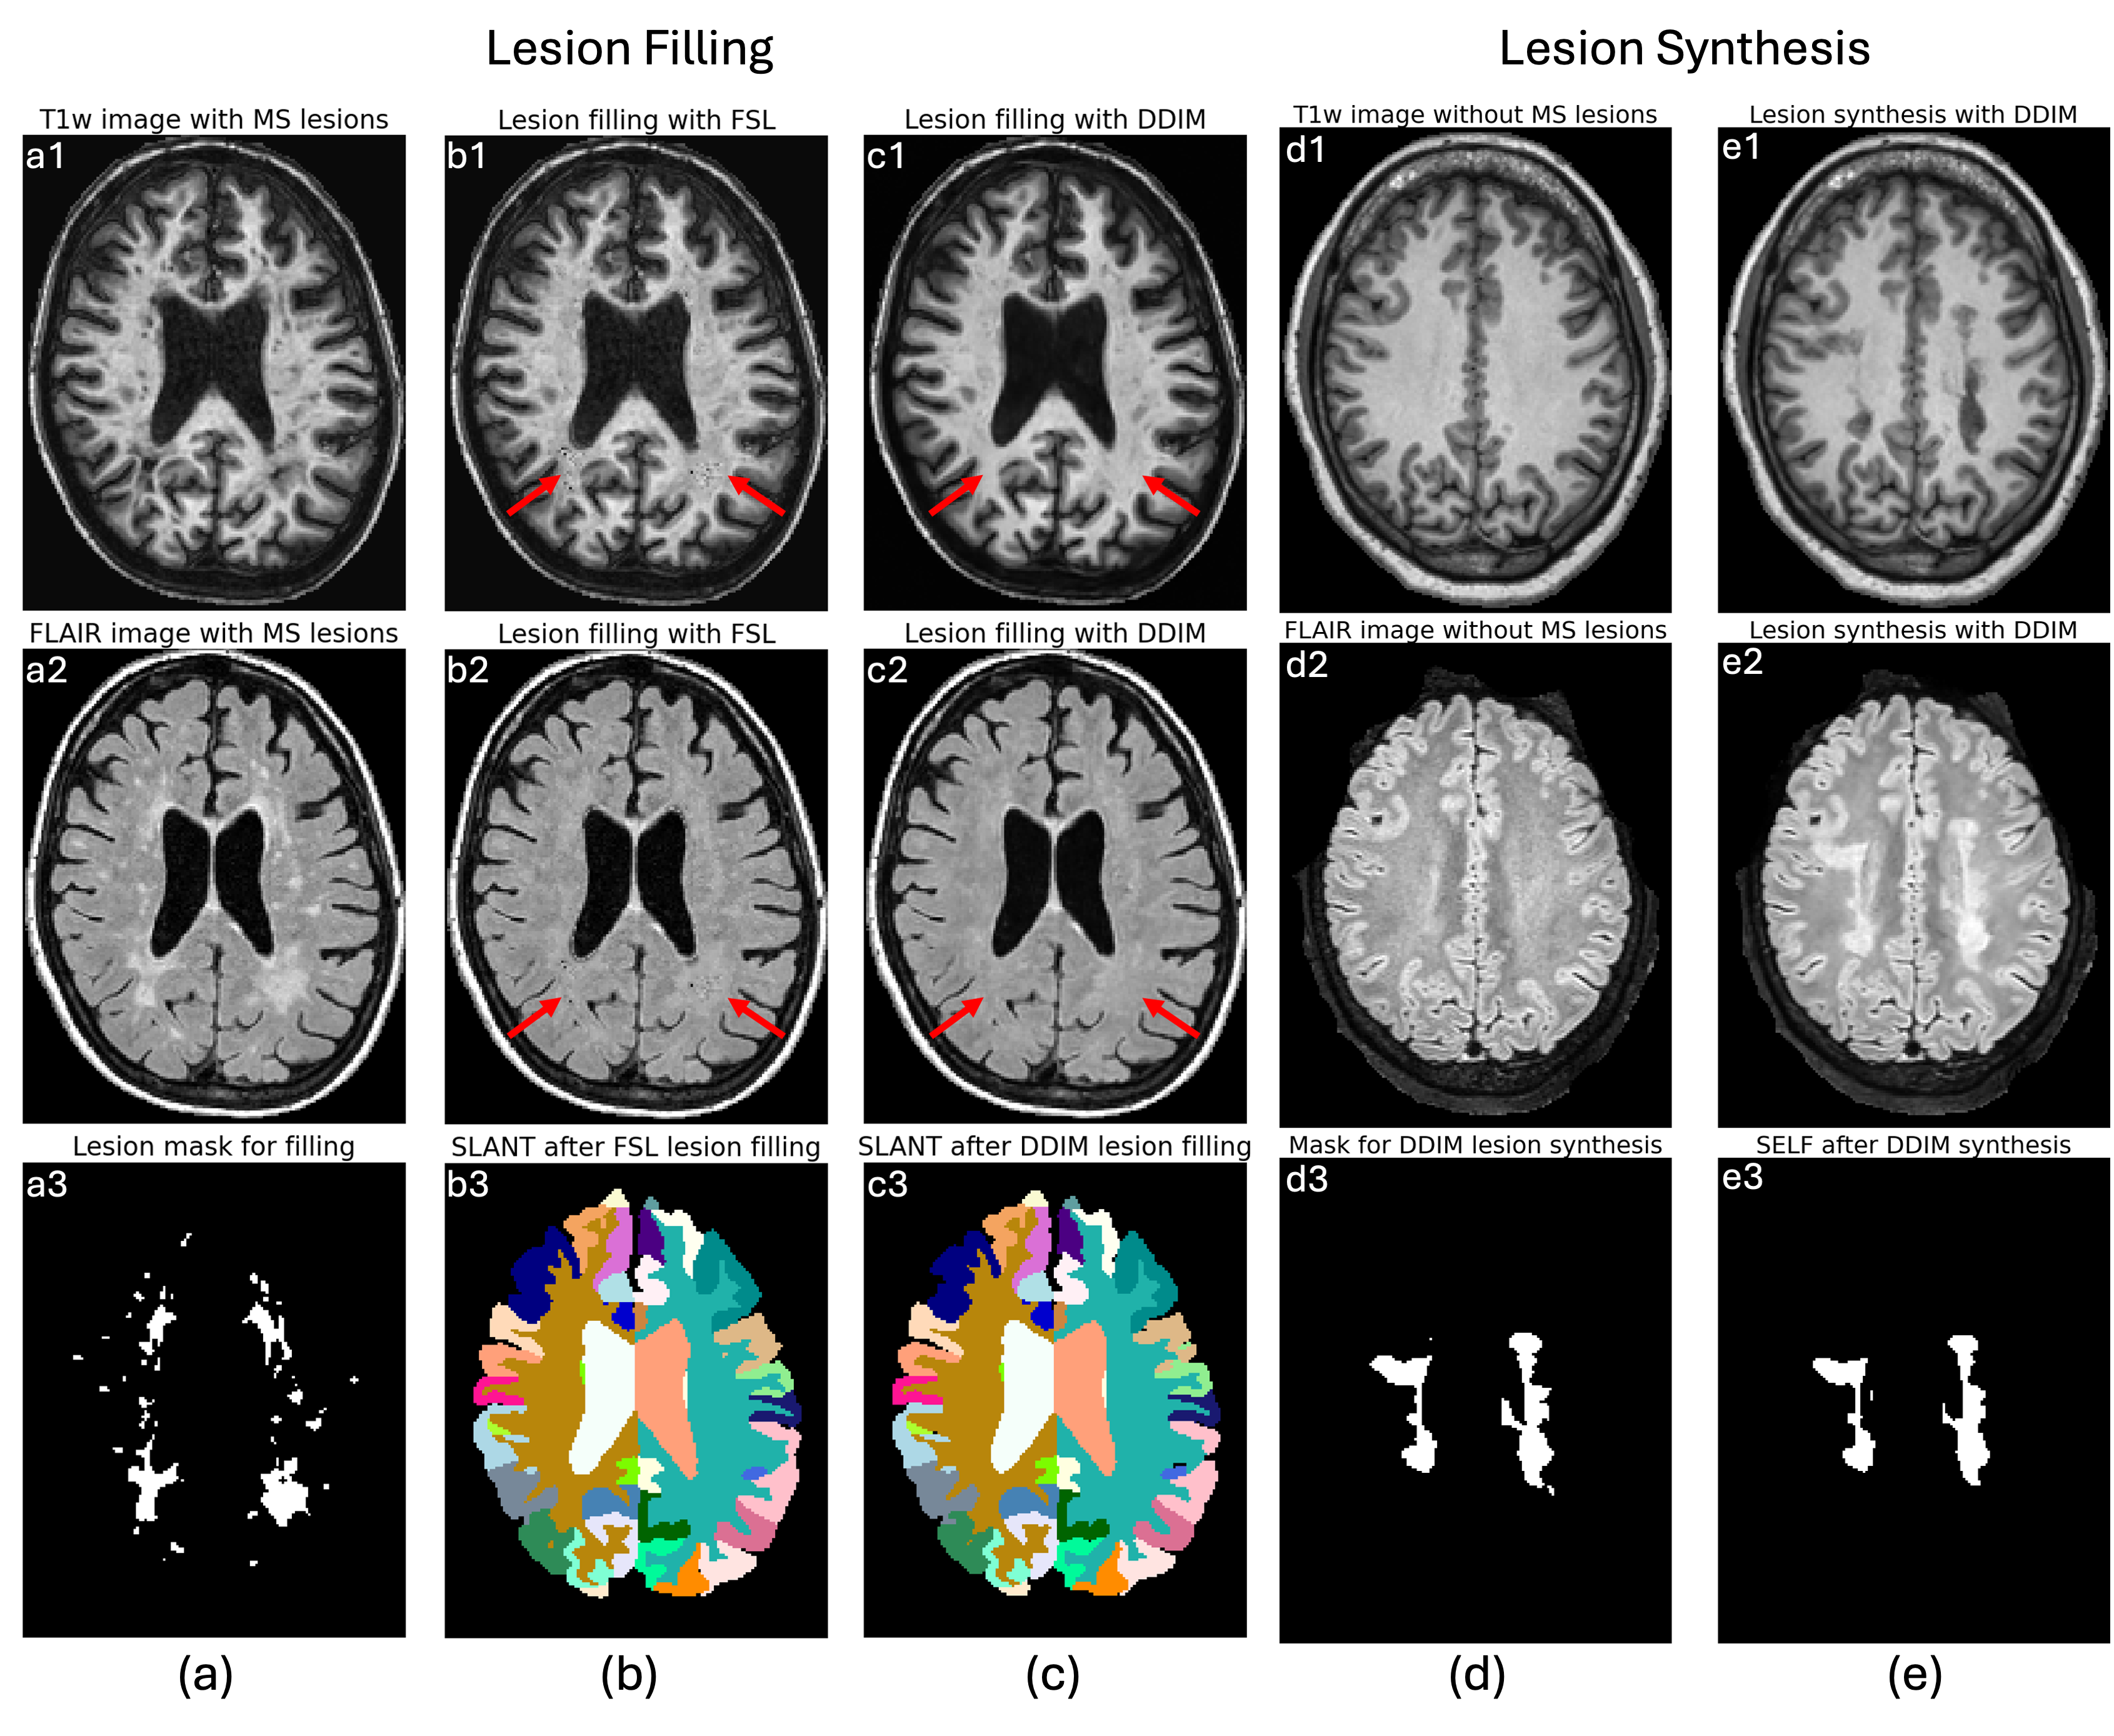

Figure 2: (a)-(c): Lesion filling results. (a1-3): Original T1w, FLAIR, and lesion mask. (b1-3): Lesion filling of T1w and FLAIR by FSL and the corresponding SLANT brain parcellation on lesion-filled T1w image. (c1-3): Lesion filling results using the proposed method and the corresponding brain parcellation. (d)-(e): Lesion Synthesis results. (d1-3): T1w and FLAIR images from a healthy subject, and the binary lesion mask for the lesion synthesis task. (e1-3): Synthetic T1w and FLAIR images with lesions, and the corresponding lesion segmentation mask.

Lesion Filling: In Fig. 2, (a) shows T1w, FLAIR, and lesion mask images of a representative MS subject. (b) shows FSL lesion filling [8] results on the T1w, FLAIR, and the SLANT [9] brain parcellation map derived from the corresponding lesion-filled T1w image, while (c) shows results for our proposed DDPM lesion filling method. The red arrows, in Fig. 2, highlight the regions of lesion infilling. Mean Dice similarity scores (DSCs) with standard deviations for regions of interest (ROIs) between SLANT using FSL and the proposed filling methods across 15 test subjects were as follows: Ventricles: 0.932 ±plus-or-minus\pm± 0.144, Cerebral White Matter: 0.915 ±plus-or-minus\pm± 0.174, Brainstem: 0.971 ±plus-or-minus\pm± 0.053, Caudate: 0.864 ±plus-or-minus\pm± 0.301, Cerebellar Gray Matter: 0.949 ±plus-or-minus\pm± 0.102, Cerebellar White Matter: 0.901 ±plus-or-minus\pm± 0.213, Putamen: 0.854 ±plus-or-minus\pm± 0.334, Thalamus: 0.936 ±plus-or-minus\pm± 0.161, and Cerebrum Gray Matter: 0.908 ±plus-or-minus\pm± 0.188.

Lesion Synthesis: In Fig. 2, (d) shows the T1w and FLAIR images of a representative healthy subject, along with the corresponding binary mask used for lesion synthesis. (e) shows the T1w and FLAIR images with synthetic lesions, and the corresponding SELF lesion segmentation mask after applying SELF on the synthetic T1w and FLAIR pair. Realistic lesions were generated with white matter hypo-intensity on the T1w image and hyper-intensity on the FLAIR image, see Figs. 2(e1) and (e2) respectively. Lesion segmentation (Fig. 2(e3)) from the synthetic T1w and FLAIR images shows a generally consistent lesion mask, compared to the original lesion mask used for synthesis, see Fig. 2(d3). A mean DSC of 0.832 (±plus-or-minus\pm± 0.049) across 10 test subjects was achieved between the segmented lesion mask from synthetic images and the original lesion mask used for synthesis.

In this work, we present preliminary results of bi-directional lesion filling and synthesis using a single trained DDPM model with DDIM-based inference acceleration. In the lesion filling task, DDIM generates regions filled with normal appearing white matter tissue contrast (red arrows in Fig. 2(c)), which can be attributed to the DDPM training process using reliable lesion masks that correspond to lesion regions only. As a result, after DDPM training, the non-lesion regions will be filled with normal appearing white matter resembling that of the training dataset. For the downstream whole-brain parcellation, some inconsistencies between the SLANT results of FSL lesion filling and our lesion filling were observed, this is an area for further analysis. In the lesion synthesis task, DDIM generates realistic lesions in both T1w and FLAIR images (Figs. 2(e1) and (e2)) with high DSCs after lesion segmentation on the synthetic images. Such synthetic images with ground truth lesion masks could be useful for training more domain-generalizable lesion segmentation models [10].